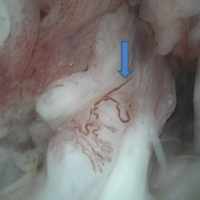

Histopathological examination revealed Gray-brown soft-tissue pieces with three blackish soft-tissue pieces from the neck of the femur containing brownish gelatinous fluid. On microscopic examination, the sections from the neck of the femur showed necrotic bone, granulation tissue, hemorrhage, and hemosiderin-laden macrophages. Sections from the cyst showed connective tissue, histiocytes, and hemosiderin pigment, suggestive of a unicameral bone cyst (Fig. 4).

Figure 4: Histopathological image of a biopsy specimen’s Unicameral bone cyst confirms the diagnosis, with the black arrow suggesting hemosiderin-laden macrophages and fibroblasts, whereas the blue arrow suggests osteoblasts and osteoclasts.